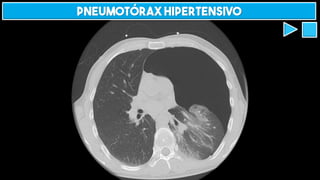

Pneumotórax hipertensivo